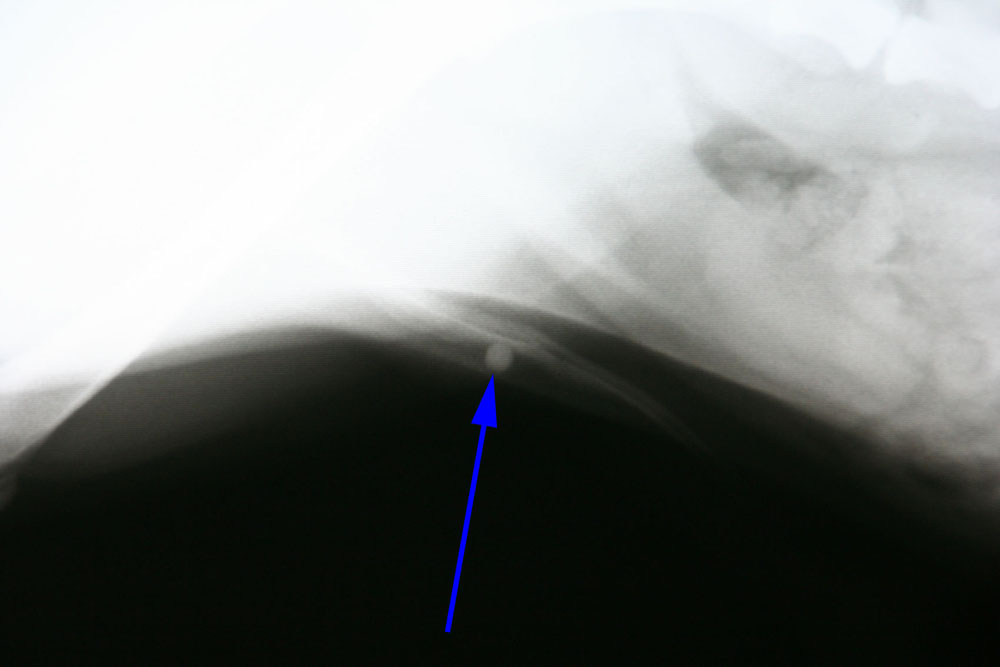

Hierna hebben we een urinekatheter ingebracht die na 4 cm vastliep op een harde structuur. Op de röntgenfoto is er bij de pijl een blaassteen te zien die vastgelopen is in het penisbotje.